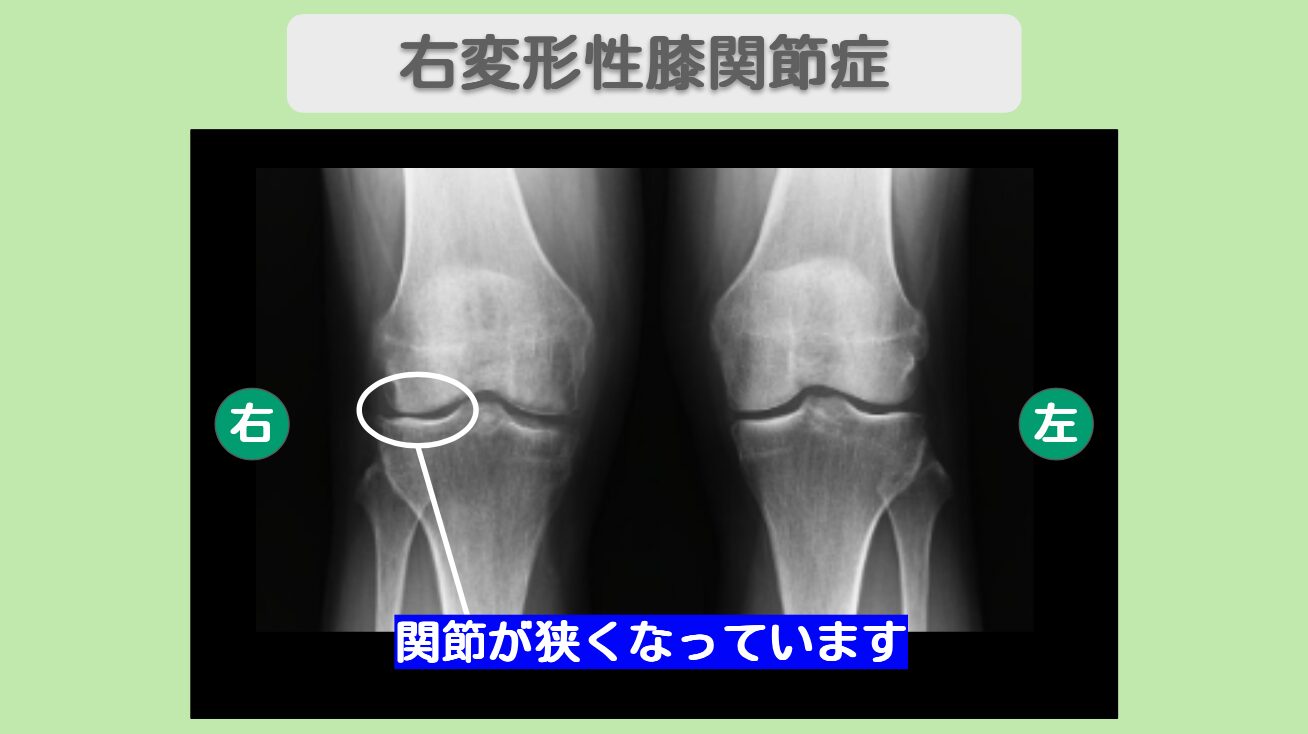

MRI・レントゲン所見

MRIにて半月板後節の損傷を認めます。